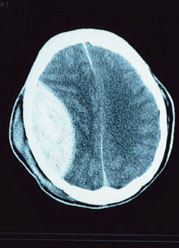

先日とは反対に、静香さんの車に乗って埼玉医大総合医療センターへと向かう。  やがて田園地帯の中にそびえ立つ医療センターが見えてきた。  ママの死の宣告が一刻一刻と近づいてくるようで身体が震えてしようがなかった。  それから一時間後。  ボクは主治医の先生から、臓器移植に関わる説明を受けていた。 「これが今朝撮影したばかりの君のママの脳の断層写真だよ」  と言いながら、ライティングボードに写真フィルムを貼り付けた。  ボードの光に照らされて脳の映像がくっきりと浮かび上がった。 「そしてこっちが、ここへ運び込まれたばかりのもの」  と、さらにもう一枚。 「事故直後のものから説明しよう。まず注目してほしいのが右脳と左脳との境にある正中 線だよ。正中線は本来、脳の中心にあるものだが、片側に大きく偏っているのが判るだろ う? これは事故の際に頭部に大きな衝撃を受けて、脳全体が左脳の方へ動いてしまった 事を示している。この時に呼吸中枢を司る延髄などの脳幹部が大きな損傷を受けて、自発 呼吸のできない植物人間状態に陥ったことが確認された。仮に脳幹部が助かっていたとし ても、これだけ大きく動いてしまったのは、左脳にとっては致命的だ。ほんの少し動いた だけでも麻痺が残るもの、この場合は右半身麻痺となるがね。……と、事故直後の断層写 真が物語る事実だよ。ここまでは判るかな?」  脳が臓器の中でも、特にデリケートなことは知っている。  物理的な衝撃だけでなくとも、精神的な衝撃を受けても壊れてしまうことも。  詳しいことまでは判らないが、写真に見るとおりに大きく偏っているのを見せられては、 真実を納得させるには十分な証拠だった。 「うん……」  ボクは静かにうなづくしかなかった。 「それでは次の断層写真。今朝撮ったものだが、さっきのと違いが判るかな?」  と、尋ねてきた。  両方の断層写真を見比べてみる。 断層写真  違いはすぐに判った。 「画像がぼやけてる……」  すぐに主治医が説明に入った。 「その通りだよ。ぼやけていると言ったが、画像がぼやけているのではなくて、脳内血腫 によって血管からの出血や、組織からの浸潤による浮腫によって、脳全体が圧迫されて破 壊されてきているんだよ。もちろん脳表面にあるはずの皺も消失している」  断層写真を見せられて解説を受ければ、もはやママの完全なる脳死状態を認識しないで はいられない。 「さて、ここから本題に入るよ。断層写真に見るとおりに、君のママの脳死は明白なる事 実だよ。臓器移植法におけるその他の確認すべき事項もすべて脳死状態を示しているんだ。 そして昨夜における判定会議において脳死の確認と、臓器移植が決定された」